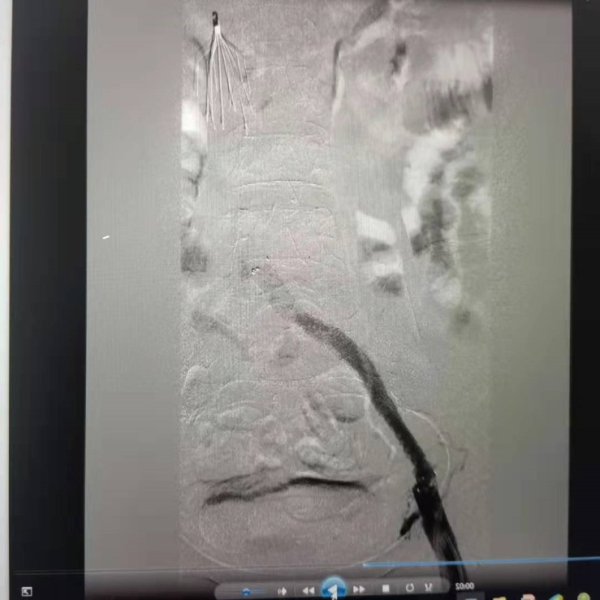

在手术过程中,马永恩医生发现患者存在左髂静脉压迫综合征(这是左下肢深静脉血栓形成的罪魁祸首),与邓女士沟通病情后后行左髂静脉球囊扩张及支架植入术,手术完成 48小时后复查血管造影,残余血栓几乎完全消散,遂撤出溶栓导管。患者经过观察,未出现任何异常,肿胀的大腿也明显恢复,患者顺利出院。